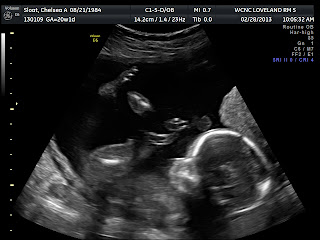

We had a lady technician and she warmed up but she was all business at first. I waited for her announcement of the gender, I wasn't sure how she would do it. It seemed for a while she couldn't get the right angle and the baby wasn't letting us see what we needed. She finally said, "Looks like we've got girl parts." What?! That didn't seem like a confident call, so I said, "really, do you know for sure? How do you know!?" She seemed surprised by my response and said, "I just do this everyday!" I laughed, okay, alright, I was just making sure. You hear a lot of horror stories about mistakes or the technician not being able to see what the sex is. I teared up, I enjoyed all the little things we got to see in the ultrasound. She moved a lot during the ultrasound, at this point I had been feeling her move for exactly two weeks. I first felt her move on Valentine's day! The technician thought that was weird. Maybe she just thought I was crazy! So funny. She told me that was unusual, I thought, are you sure? My doctor told me it was likely that I would feel her move before the next 20 week appointment. Greg had felt her move just a few days after I had felt her move. We saw her flip, lick the umbilical cord, move around, stretch, etc. It was so cute and with all the ohh...ahhs, etc. I think the technician even joined in! It was so neat to "meet" her for the first time.

This is her chest on the left and you can see her heart with the two chambers and her ribs. On the right, you see her face. You can see where her eyes are, the nose, and her hands up by her face. Ohh...so cute.

Profile pictures!!! Those little bubbles you see right above her nose, that is the umbilical cord.

Stats: 11 oz, 20 weeks and 1 day, 155 bpm